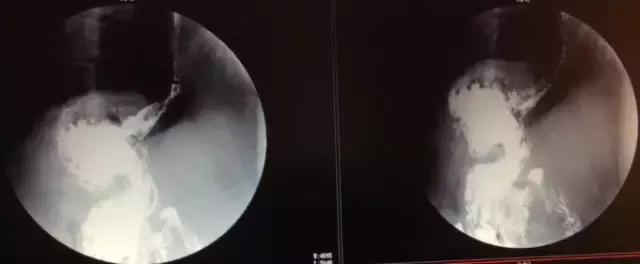

患者男性68岁,主因消瘦2个月,腹部不适入院就诊。详细检查报告及影像资料如下:

中晚期胃底贲门腺癌,诊断已明确。治疗方案有